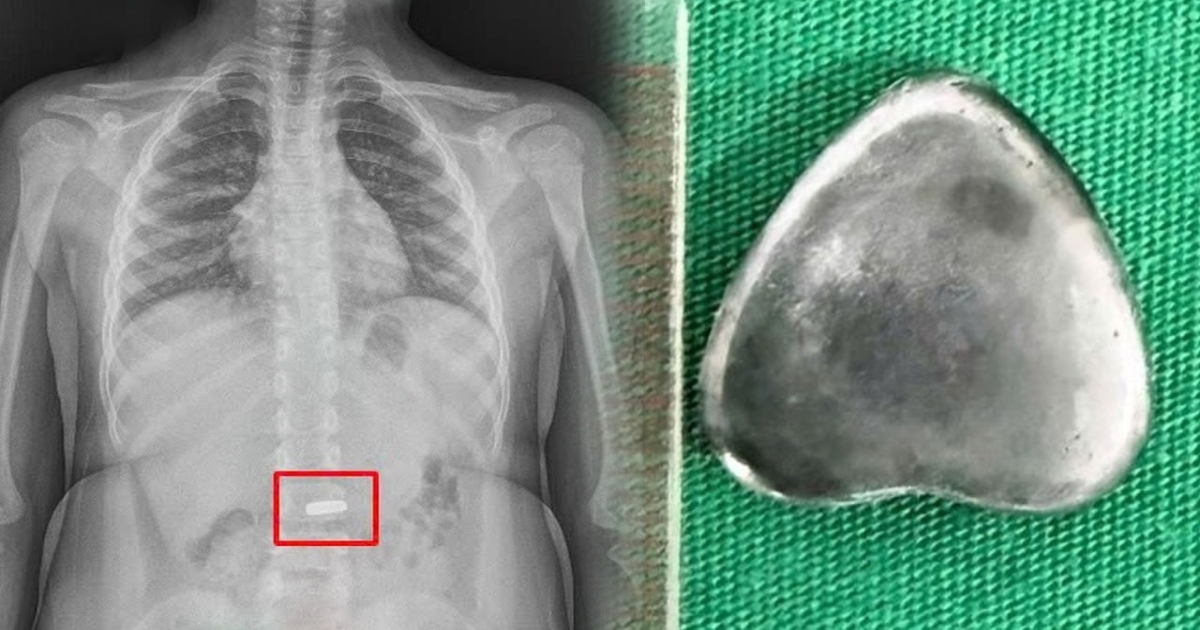

வியட்நாமில் ஆறு வயது சிறுவன் விளையாடிக்கொண்டிருந்தபோது, தவறுதலாக 2 செ.மீ நீளமுள்ள இதய வடிவ காந்தம் ஒன்றை விழுங்கினார். பெற்றோர் உடனடியாக அதை கவனித்து அருகிலுள்ள மருத்துவமனைக்கு கொண்டு சென்றனர். எக்ஸ்-ரே பரிசோதனையில் அந்த காந்தம் சிறுவனின் குடலில் சிக்கியிருப்பது தெரியவந்தது.

குடலில் துளைகள் அல்லது நெக்ரோசிஸ் ஏற்படும் அபாயம் இருந்ததால், வியட்நாமின் வின்-லாங்கில் உள்ள ஜுயென் பொது மருத்துவமனையில் மருத்துவர்கள் அவசரமாக எண்டோஸ்கோபி செய்து அந்த காந்தத்தை வெற்றிகரமாக அகற்றினர். சிகிச்சைக்குப் பிறகு சிறுவனுக்கு எந்த காயமும் ஏற்படவில்லை. அன்று மாலையே அவர் டிஸ்சார்ஜ் செய்யப்பட்டார்.